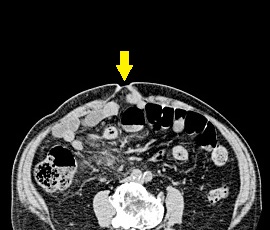

腹痛と嘔吐を主訴に精査加療目的に受診。その前に膵体尾部嚢胞に対して腹腔鏡補助下膵体尾部切除術を施行。 CT検査にて、腹壁にヘルニアを認め腹壁瘢痕ヘルニアと診断。 手術(腹腔鏡下ヘルニア手術)を施行した。

CT画像